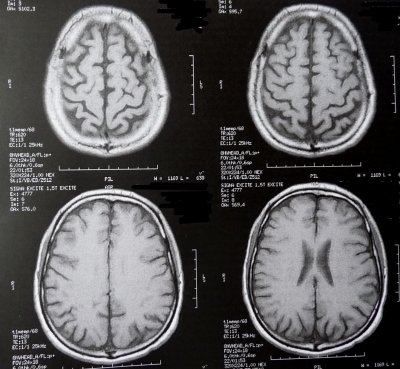

Sie sind hier: Startseite Nachrichten Wissenschaft US-Studie: Gehirnscans sagen Gewichtszunahme und Sexualverhalten voraus Bild: Dieter Schütz / pixelio.de